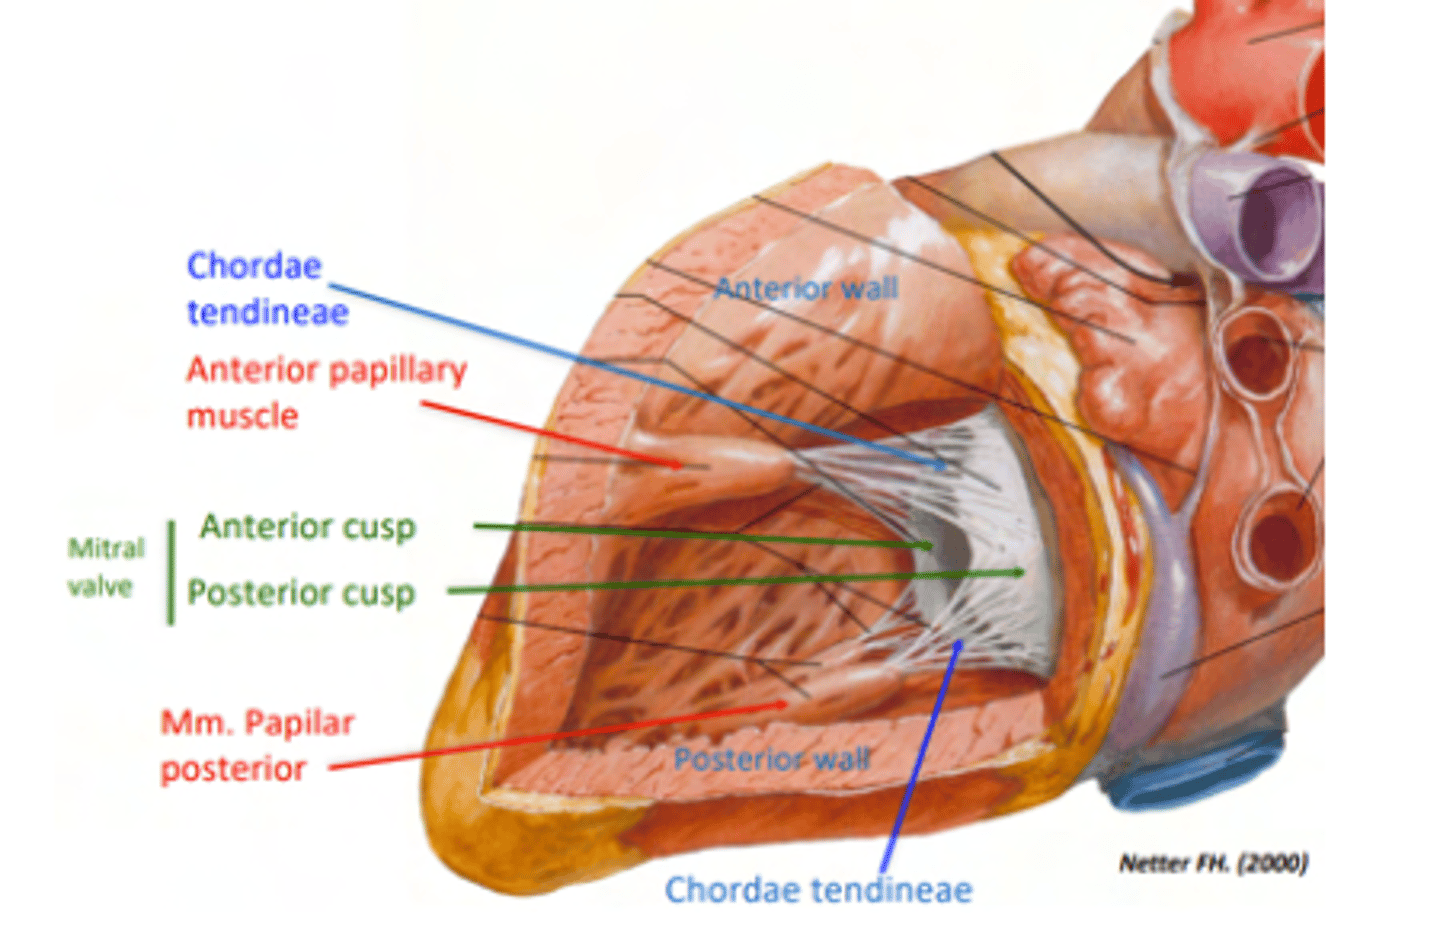

What are the valves separating atrium and ventricle?

. Mitral or bicuspid valve (left atrioventricular valve, 2 cusps)

What is the valve in the AV left canal?

. Mitral valve

2 cusps (anterior and posterior) and 2 associated papillary muscles

What prevents backflow of blood from the left ventricle to the left atrium?

mitral valve or biscuspid valve

consisting of two cusps connected to two papillary muscles,

What role do the papillary muscles and chordae tendineae play in the function of the tricuspid valve?

During ventricular systole (contraction), the tricuspid valve closes

The papillary muscles contract at the same time as the ventricle.

This contraction tightens the chordae tendineae, pulling the valve leaflets taut and holding them in place.

This mechanism prevents the valve leaflets from prolapsing (bulging back) into the atrium under the high pressure of ventricular contraction.